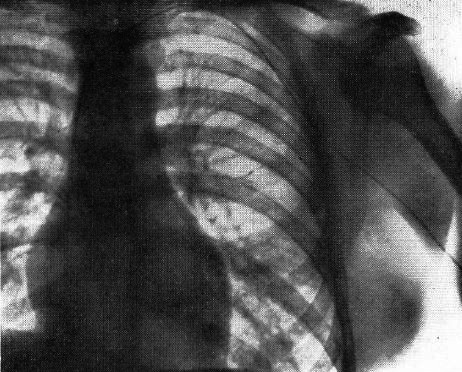

図1. Forssmannが行なった自己人体実験.左上肢静脈から右心房に挿入されたカテーテルが見える.

【要旨】 緊急時の心腔内薬剤投与法の新しい方法として,静脈系から右心系へのカテーテル挿入を試みた.屍体による実験を経て,自らを実験台としてこれを試した.肘静脈を穿刺し,ここから尿管カテーテルを挿入した.カテーテルの移動に伴い軽度の温感を感じた他は副作用はなかった.カテーテルを挿入した状態でレントゲン撮影室に移動して撮影したところ,カテーテルが右心房に達していることを確認した(図1).

臨床例として,高度の循環障害の患者の心腔内にこの方法でアドレナリンなどの薬剤を投与し,症状の改善をみた.かくして,右心系へのカテーテル挿入は安全であることが証明できた.